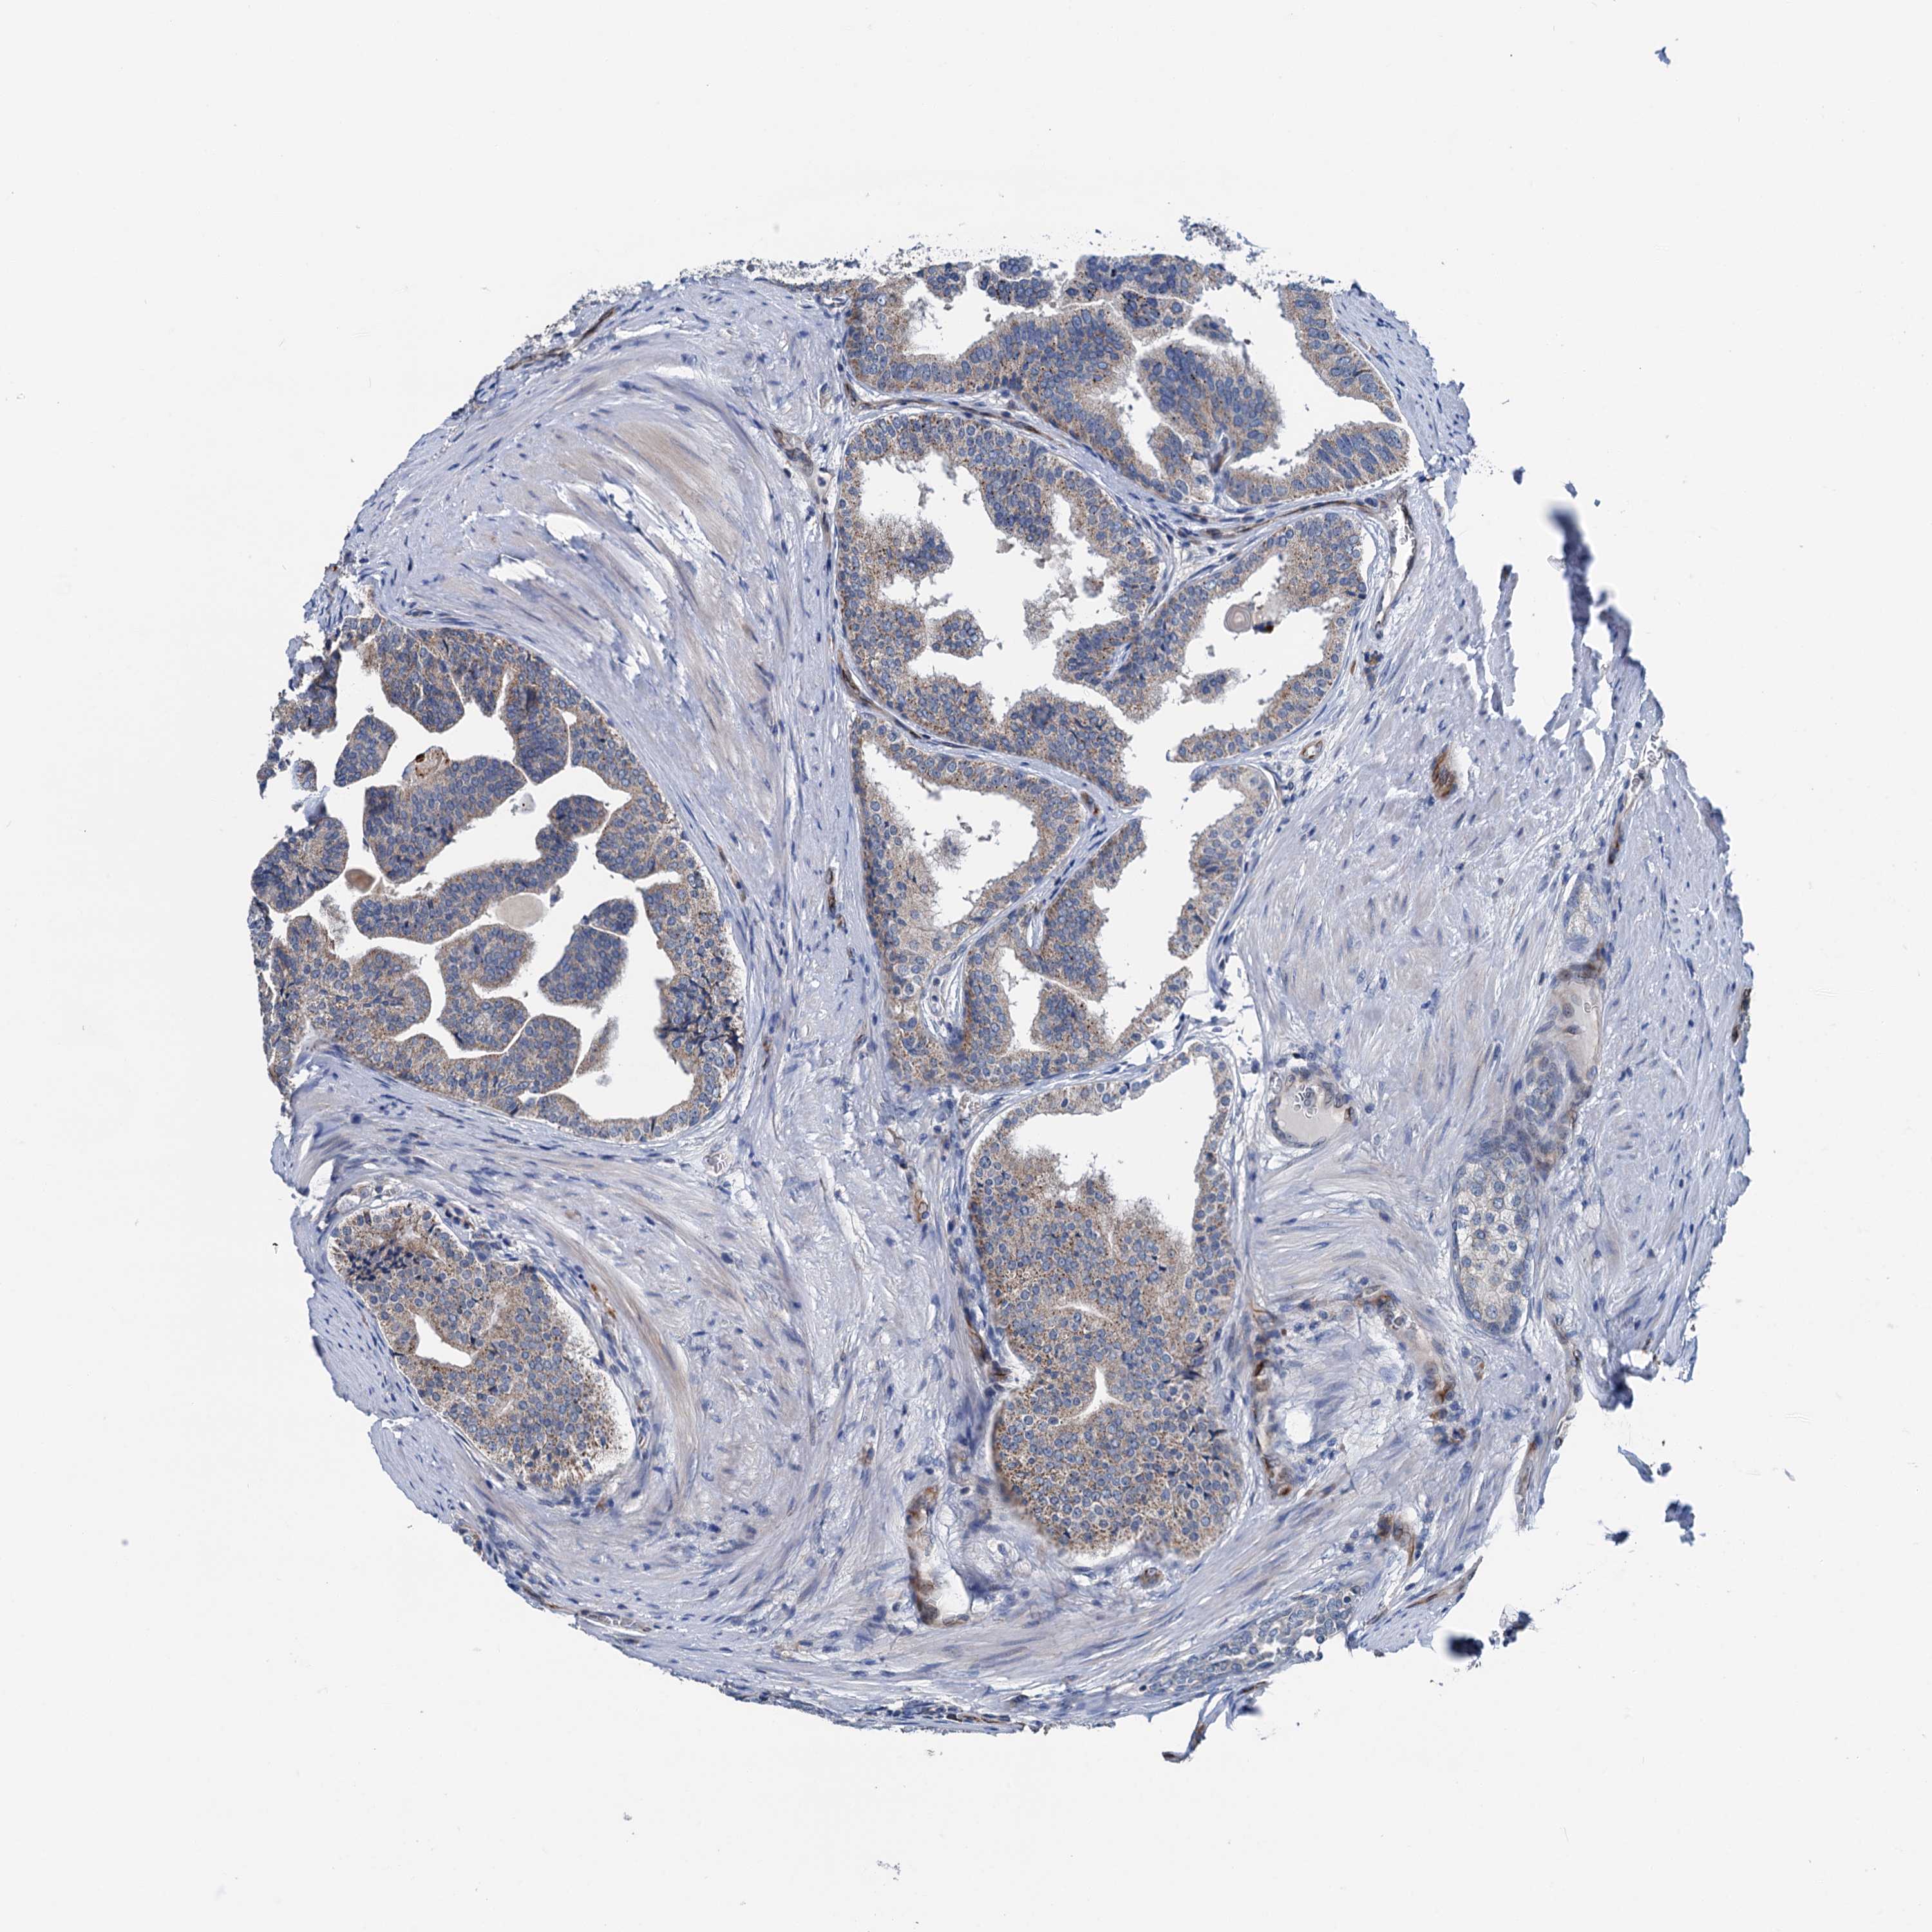

PROSTATE CANCER - Protein expressioni

A mouse-over function shows sample information and annotation data. Click on an image to view it in a full screen mode. Samples can be filtered based on level of antibody staining by selecting one or several of the following categories: high, medium, low and not detected. The assay and annotation is described here.

Note that samples used for immunohistochemistry by the Human Protein Atlas do not correspond to samples in the TCGA dataset.

Antibody stainingi

Antibody staining in the annotated cell types in the current human tissue is reported as not detected, low, medium, or high, based on conventional immunohistochemistry profiling in selected tissues. This score is based on the combination of the staining intensity and fraction of stained cells.

Each image is clickable and will lead to virtual microscopy that enables deeper exploration of all samples and also displays staining intensity scores, fraction scores and subcellular localization as well as patient and tissue information for each sample.

Antibody HPA040867

Staining

High

Medium

Low

Not detected

Intensity

Strong

Moderate

Weak

Negative

Quantity

>75%

75%-25%

<25%

None

Location

Nuclear

Cytoplasmic/membranous

Cytoplasmic/membranous,nuclear

Adenocarcinoma, NOS

Adenocarcinoma, High grade

Adenocarcinoma, Low grade